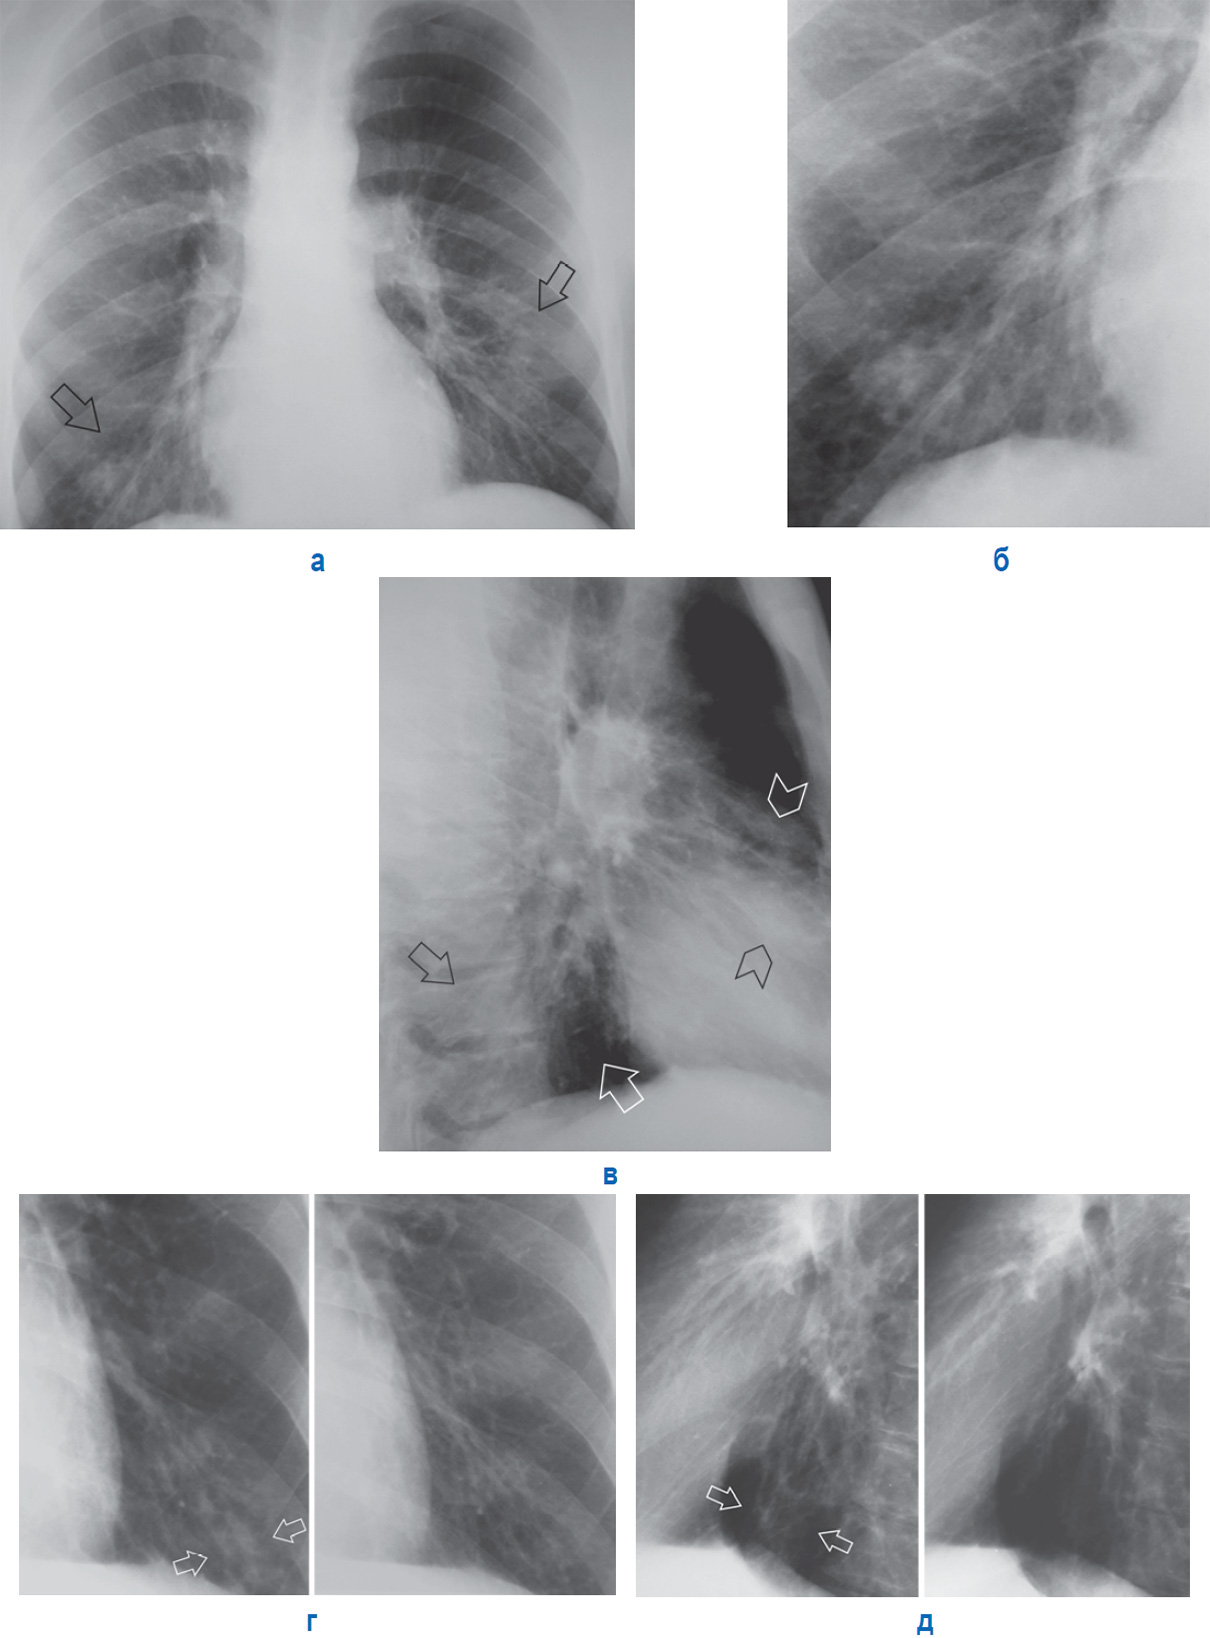

Рисунок 7. А – госпитальная двусторонняя полисегментарная пневмония (с обеих сторон отмечается очаговая и перибронховаскулярная инфильтрация на фоне усиленного рисунка: справа – наддиафрагмально, слева – в среднем, нижнем отделах легочного поля (см стрелки)). Б – область правого корня легкого (фрагмент предыдущей рентгенограммы). В – фрагмент рентгенограммы в правой боковой проекции (тот же пациент): очаговая и перибронховаскулярная инфильтрация в базальных сегментах нижней доли (см стрелки) и в проекции язычковых сегментов слева (см указатели).

Г и Д – Пневмония в нижней доле слева (фрагменты рентгенограммы другого пациента): периваскулярная инфильтрация (см стрелки) до и после лечения. Г – фрагмент рентгенограммы в прямой проекции. Д – фрагмент рентгенограммы в левой боковой проекции